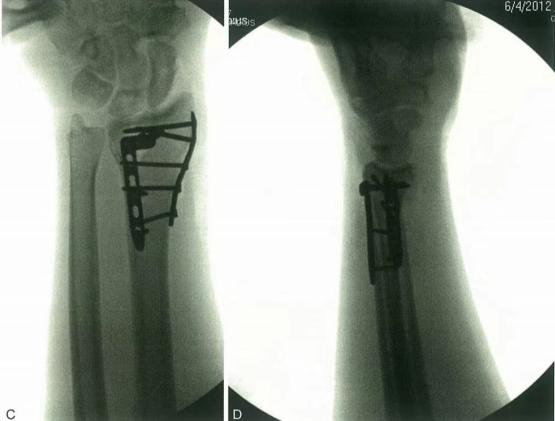

- 4-cm vzdolžni rez se naredi dorzalno na tretje metakarpalno steblo in tetiva iztegovalke sredinca se skrči, da se izpostavi tretja metakarpalna stebla;

- Drugi 4-cm rez se naredi vsaj 4 cm dorzalno od zdrobljenega polmera;

- Tretji 2-cm dorzalni rez se naredi na Listerjevem vozlu, da se izpostavi tetiva extensor hallucis longus.

Iz distalnega reza se vlečna plošča vstavi proksimalno vzdolž ravnine med tetivo ekstenzorja (četrti dorzalni predel), sklepno ovojnico in pokostnico. Tetivo iztegovalke lahko po potrebi premaknemo.